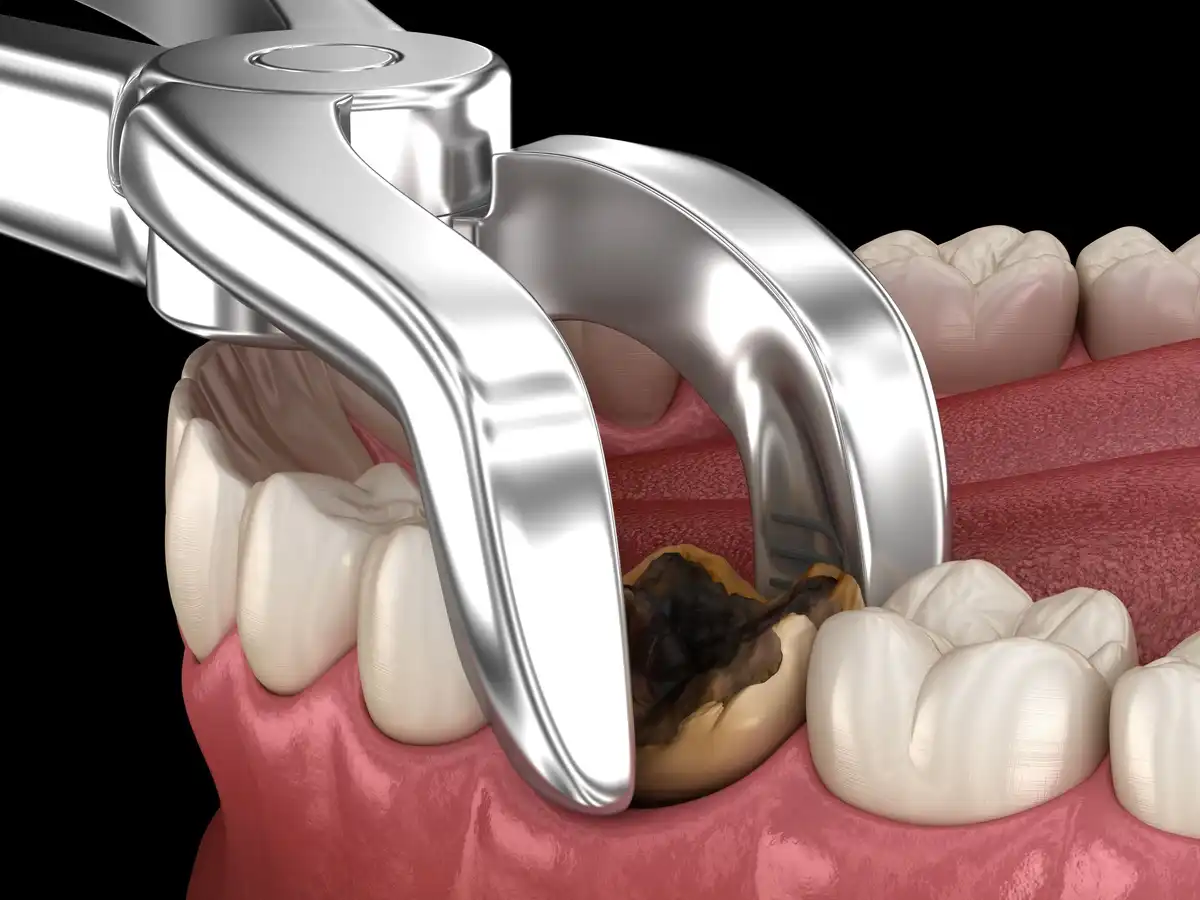

Wisdom teeth pain can be difficult. Wisdom teeth extraction is performed by a dentist or oral surgeon with or without sedation or general anesthesia.Wisdom Teeth Stitches Care | Healing Time, & Infection Risks

During wisdom teeth removal, stitches aren’t always a given. Much of it will depend on the type of extraction you’re having and how it’s being completed.Cost to Extract a Tooth With & Without Insurance

The average price of a simple tooth extraction without insurance costs between $100 to $300 per tooth. Sedation wisdom tooth extraction costs $1,000 or more.